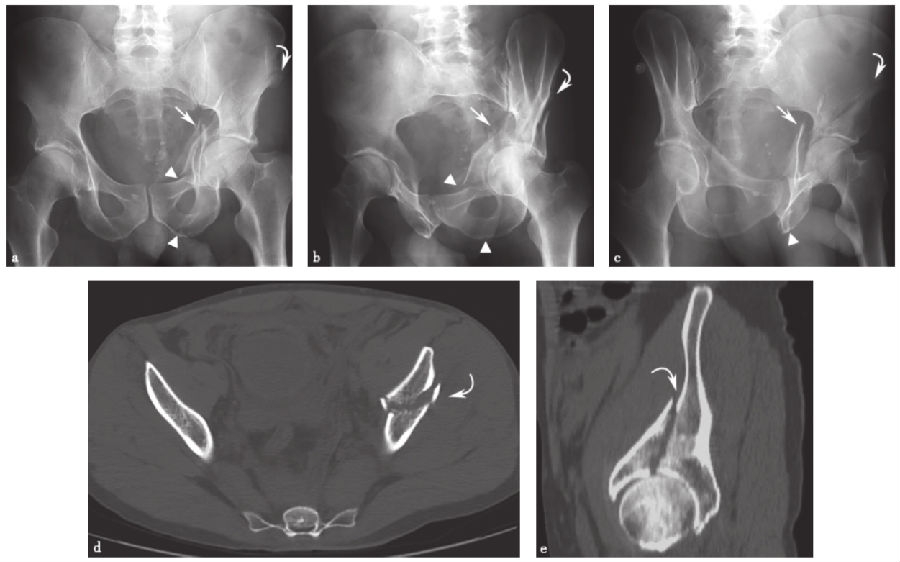

2、T形髋臼骨折:

T形髋臼骨折(图11)是一种横向髋臼骨折并向下延伸至闭孔环的组合。它类似于双柱断裂,因为它破坏了闭孔环;另一种相似性是髂耻线和髂坐线的破坏。然而,骨折并不涉及髂骨翼,这有别于双柱骨折。

图11 T形髋臼骨折a.骨盆正位X线片;b、c.双侧斜位骨盆X线片;d.轴向CT扫描;e.髋臼侧面三维CT扫描,右侧半骨盆和股骨去除。图中箭头示闭孔环骨折,直线箭头示通过髋臼的横行分量。注意CT扫描时横向髋臼骨折成分的特征性斜向矢状取向,X线片上横向相对于髋臼。

横行骨折线实际上并不在解剖学的横行平面内,而是横行于髋臼。由于髋臼的杯形通常向下和向前倾斜,所以横向断裂面呈现类似的取向。因此,在X线片上,破坏髂耻骨和髂骨线的骨折线在髋臼斜平面的上方和内侧走行。通过观察髋臼面,这是最好的评价。在CT上,这种横向骨折成分被看作是从髋臼内侧和上方走行的矢状骨折。

3、横行髋臼骨折:

髋臼的横行骨折(图12)仅限于髋臼,而不涉及闭孔环。横行髋臼骨折必须涉及髋臼的前部和后部,因此髂耻线和髂坐线在X线片上显示不连续。该骨折线从髋臼向上和向内延伸。在CT上,当从下向上滚动时,在后续的CT图像上可以看到特征性的矢状面骨折线向内侧移动。尽管在解剖学上不是横行的,但断裂平面相对于髋臼是横行的,其在下部和前部相对倾斜。在髋臼面的CT重建图像上可以最清楚地看到这种骨折面走向。

图12 横行髋臼骨折a.骨盆正位X线片;b、c.双侧斜位骨盆X线片;d.轴向CT扫描;e.右侧髋臼三维CT重建侧面观显示骨折走向(直线箭头)横向于髋臼,破坏髂耻线和髂坐线(箭头)。注意CT扫描时特征性的矢状-斜向骨折平面(d)。箭头示破坏的髂耻线和髂坐线,直线箭头示横向于髋臼的骨折线。

4、横行后壁骨折:

横行后壁骨折(图13)是一种前面描述的横行骨折,伴随着粉碎性的后壁骨折,这种骨折通常会被置换。与孤立的横行骨折一样,关键在于判断闭孔环是否被破坏,若闭孔环完整,则不考虑双柱和T形骨折。如同简单的横行骨折一样,这种骨折类型不会延伸到髂骨翼。

图13 横行后壁骨折a.骨盆正位X线片显示后壁髋臼骨折;b、c.双侧斜位骨盆X线片;d.轴位CT扫描;e.髋臼侧面三维CT扫描,右半骨盆和股骨去除后,显示横向骨折(直线箭头)破坏髂耻骨和髂坐线(箭头),伴有移位和粉碎的后壁骨折片段(弯曲的箭头)。

在X线片上,髂耻线和髂坐线的破坏与孤立的横行骨折一样。然而,与孤立的横行骨折不同,可以看到额外的后壁粉碎。在没有移位的情况下,由于碎片重叠在股骨头上,所以在前后位X线片上很难识别后壁的粉碎。倾斜Judet位X线片和CT有助于显示粉碎的后壁组件。